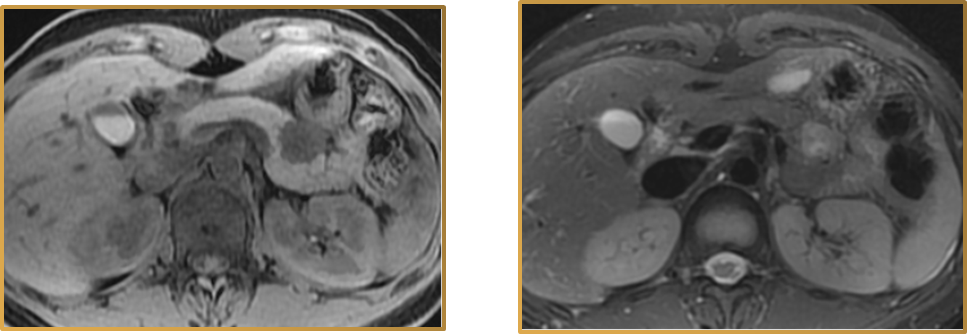

13.包膜征

实性假乳头状肿瘤(SPN)。小病灶包膜较模糊,大病灶包膜清晰。

14.假包膜征

腺泡细胞癌、实性浆液性囊腺瘤(SCN)、肝样腺癌。